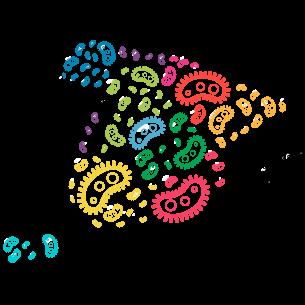

El Mapa Epidemiológico desarrollado por el PRAN es una herramienta de acceso restringido para usuarios registrados (veterinarios clínicos o laboratorios) y está diseñada específicamente para facilitar una prescripción más racional de antibióticos. Su utilidad es múltiple:

El Mapa Epidemiológico es una herramienta digital interactiva que representa un puente entre:

Probablemente será una herramienta indispensable en la clínica veterinaria del futuro, donde los profesionales pueden consultar información epidemiológica detallada, como:

La frecuencia de aislamiento en el tiempo por región, especie animal y bacteria.

Los porcentajes de sensibilidad para diferentes antibióticos.

La información epidemiológica útil para todos los casos clínicos producidos por el mismo agente patógeno, siempre que se pueda establecer un nexo epidemiológico.

La distribución geográfica de los datos.

agregada y anonimizada, se presenta en forma de gráficos, mapas y tablas comparativas de fácil interpretación para el veterinario clínico.

Figura 1. Pantalla de búsqueda del Mapa Epidemiológico del PRAN.